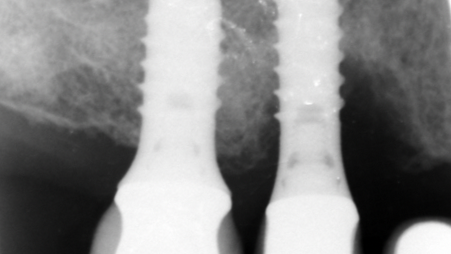

| 10:30 | Prä- und postextraktionelle radiologische Beurteilung und Planung | Prof. Dr. Dr. Bernd Stadlinger | ||